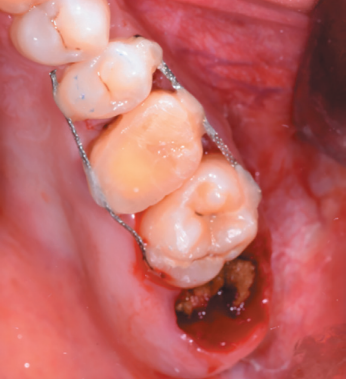

Aft er obtaining the informed consent, an anaestheti c block was performed using Arti caine 4% with Epinephrine 1:100,000 (UltracaineTM, Normon SL, Madrid, Spain) of the posterior and middle superior alveolar nerve, and anterior palati ne. An atraumati c extraction of the root remains of the 2.6 and the

curett age of the apical process (Figure 6) was performed, leaving the alveolus of the 2.6 prepared to receive the autotransplant of the 2.8 (Figure 7).

The 2.8 was then extracted with forceps (Figure 8), with minimal manipulati on of the periodontal ligament of the third molar, placing the upper third molar in the position of the upper fi rst molar (Figures 9 and 10).

2.8 transplanted in the alveolus of the 2.6.